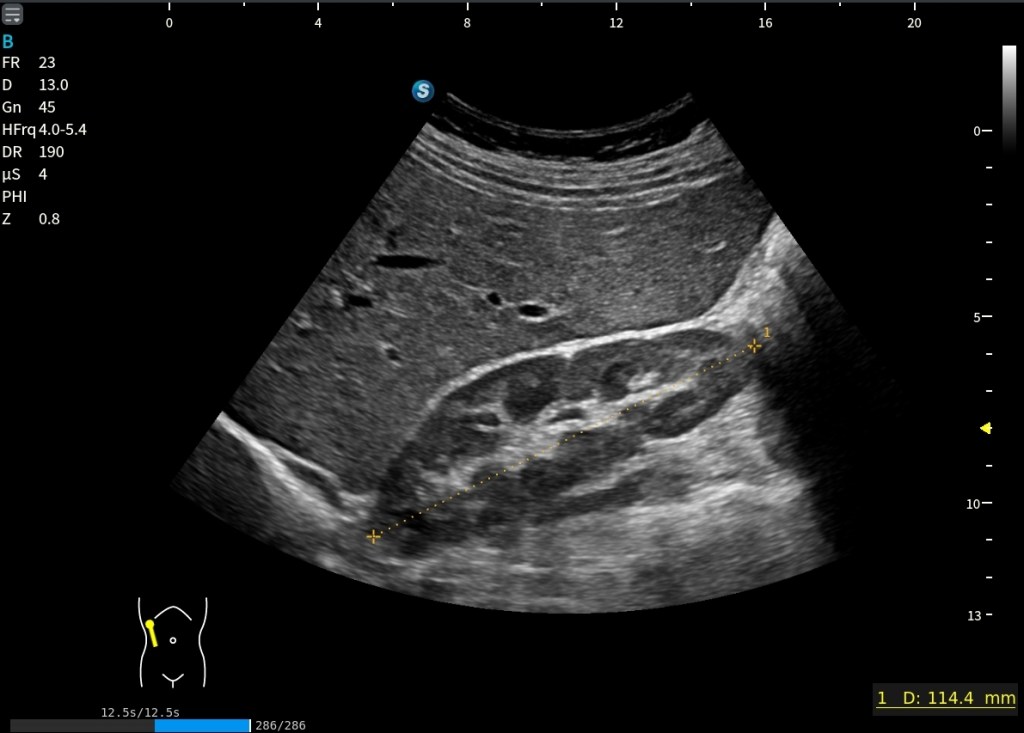

En la imagen siguiente, tenemos una inferior y una superior, en la superior estamos viendo una situación de normalidad. La corteza renal y el hígado se ven con la misma ecogenicidad. Es lo que buscamos siempre.

Sin embargo, en la imagen inferior la cosa cambia. Lo que observo es una hiperecogenicidad renal difusa del riñón derecho. El riñón se ve más brillante que el hígado de forma global, no es algo focal.

Está marcado con Normalidad y Patología.